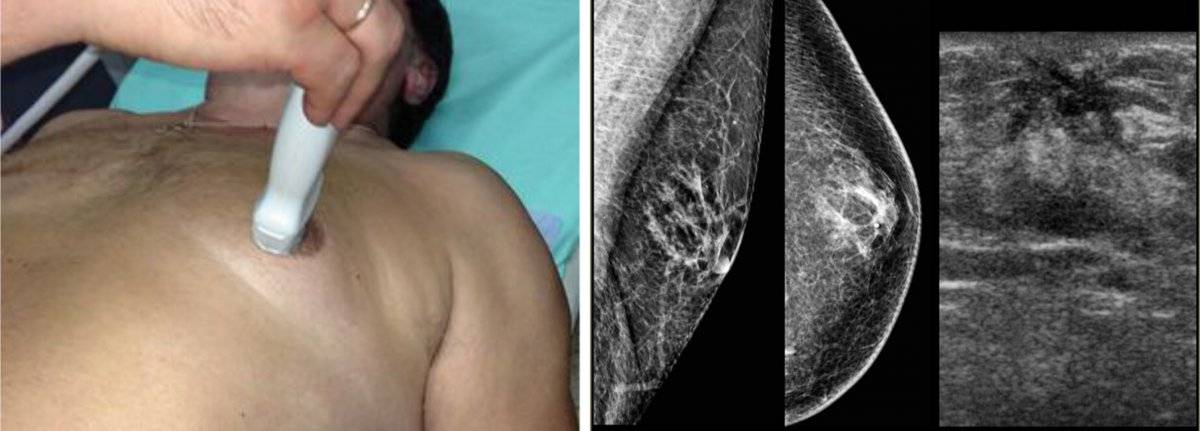

Суть операции при гинекомастии – удаление железистой ткани. Если объём удаляемой ткани большой – на несколько дней после операции может быть установлена дренажная трубка. Разрез может быть выполнен по границе тёмной части ареолы или сбоку грудной клетки (по желанию пациента).

Пациент после операции по поводу 2-х сторонней гинекомастии. Разрезы были выполнены по границе нижней части ареолы.